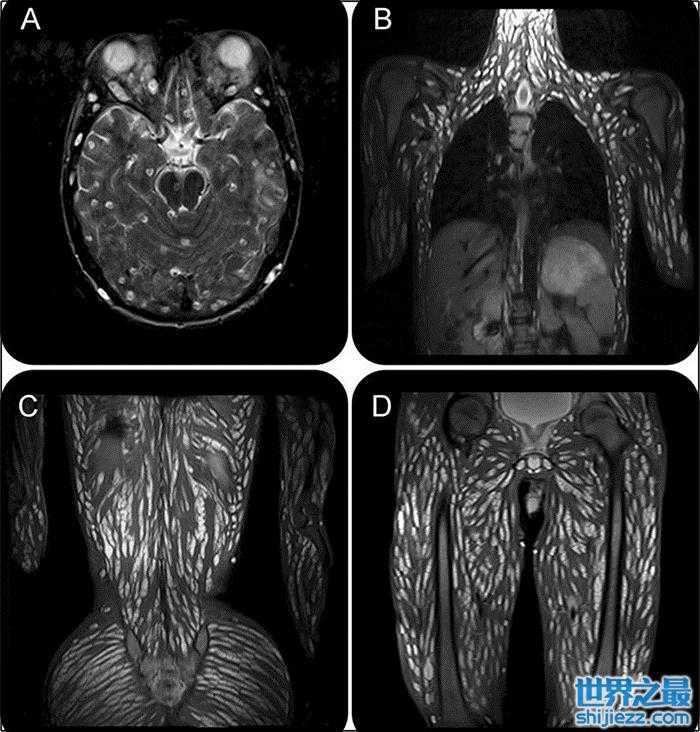

根据《诗华日报》报道,泰国一名18岁男子因出现呕吐、头痛、抽蓄及感官扭曲等症状,赶往医院求诊。医生诊断后替他进行核磁共振检查,竟发现他含头部、脑组织、胸腹部、四肢皆爬满条虫,画面相当恐怖,初步推断男子是生吃了猪肉或附有从卵的食物造成。

寄生虫研究中心PDRC在12日在网上发布了该男子的病例,经核磁共振扫描后确诊为猪囊尾蚴病(Cysticercosis,又名囊虫病)。从照片可见,男子的脑组织、头部、胸腹部、脊椎和四肢,全布满了缓缓蠕动的猪肉绦虫。